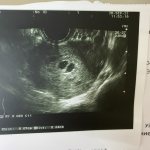

На УЗИ должна быть картина в виде множества пузырьков, типа как гроздь винограда.

Пока что здесь вижу 2 плодных яйца

Просто загуглите «пузырный занос» и посмотрите как это выглядит. У вас вообще ничего общего с этим нет. По узи просто 2 плодных яйца — двойня.